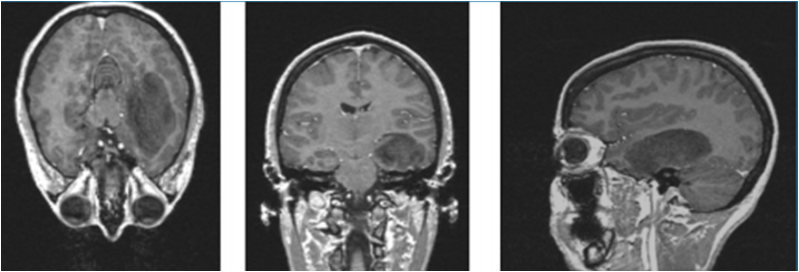

According to WHO4, the LGG grade II astrocytoma can be located as illustrated in figure 1.